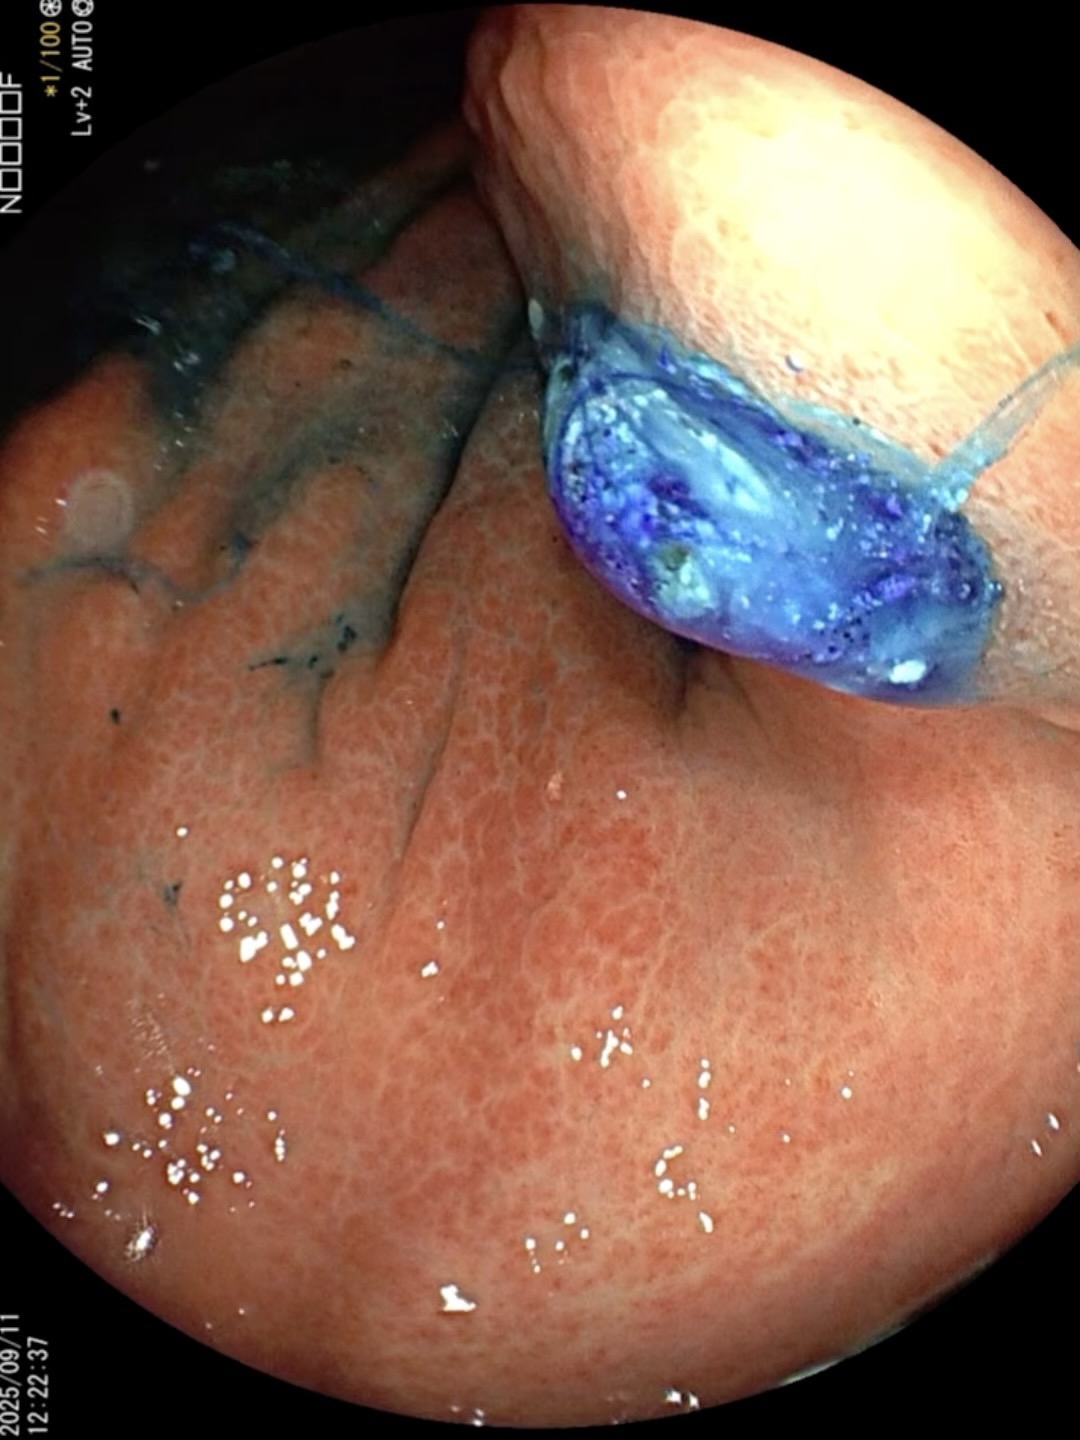

病例胃瘘口-经胃镜下诊断与治疗

患者 老年 男性,腹痛入院。

胃镜诊治如下:

胃瘘 (5)